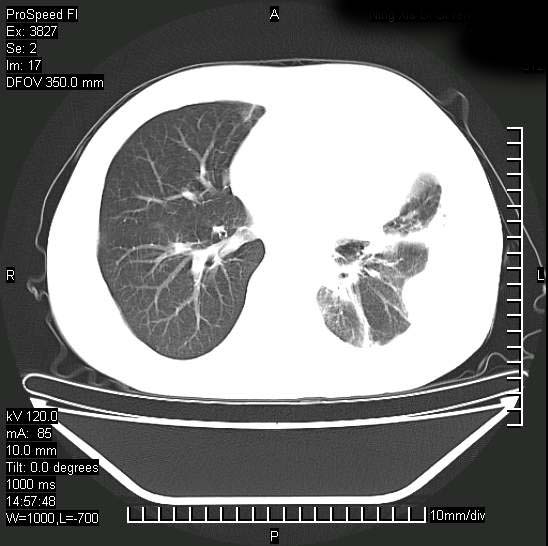

男性,一月前出现右侧肋区疼痛,较剧烈,干咳,无发热,自诉使用抗炎药后缓解,几天前又出现左侧剧烈疼痛,

发热,体温38。9,今天ct,考虑左侧包裹性脓胸,胸腔积液,右上中肺小斑片影,结核/炎症?胸水未见恶性细胞。